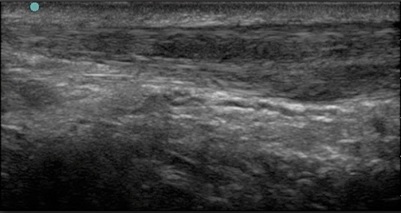

Foot & Ankle Intrasubstance Longitudinal Tearing Image